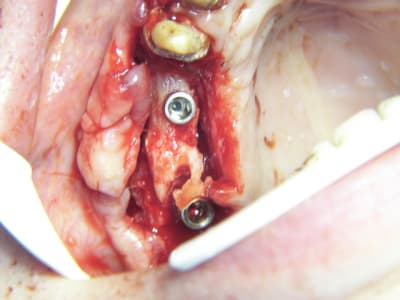

bon et bien ça c'est fait!

curetage (deux bonnes heures) dépose des deux vis d'ostéo et de l'implant en 16, nettoyage implant en 14/15 (axe un peu limite pour cause structure osseuse) et 17.

Vitalos

le greffon placé il y a 6 mois (grosse corticale) était dans le "vide" au niveau de 14, et il m'aurait fallu le piezzo éventuellement (il n'était pas installé, pour cette chir) pour "percer" la corticale sans pression, car à la fraise, je sentais le bloc plier, et nous avons préférés (avec le confrère) tenter un compromis pour la prothèse qui ne sera pas catastrophique et devrait permettre à la patient (qui a déjà subie 2 greffes, menton et ramique, avec un souvenir sympa du menton d'ailleurs)d'avoir une reconstruction fixe.

je ne sais pas si le vitalos permettra de rattraper ce cas là, mais vu tous les soucis que nous avons rencontrés pour le nettoyage (biooss infiltré dans la muqueuse de partout, j'ai du "virer" 60% du périoste et honnêtement je ne savais pas trop comment faire un "abri" de reconstruction pour l'os et l"environnement tissulaire, de façon simple.

j'avoue que j'ai une préférence, (pas encore une addiction mais presque) pour le vitalos, ou tout produit facile à appliquer, avec des précautions bien sur, et dont les résultats sont prédictibles, si il n'y a pas d'erreur à la pose, et que lors des sutures il n'y a pas de "chocs" parasitant la prise du matériaux.

photos montrant le hiatus greffe/os et pose avec vitalos à la fin